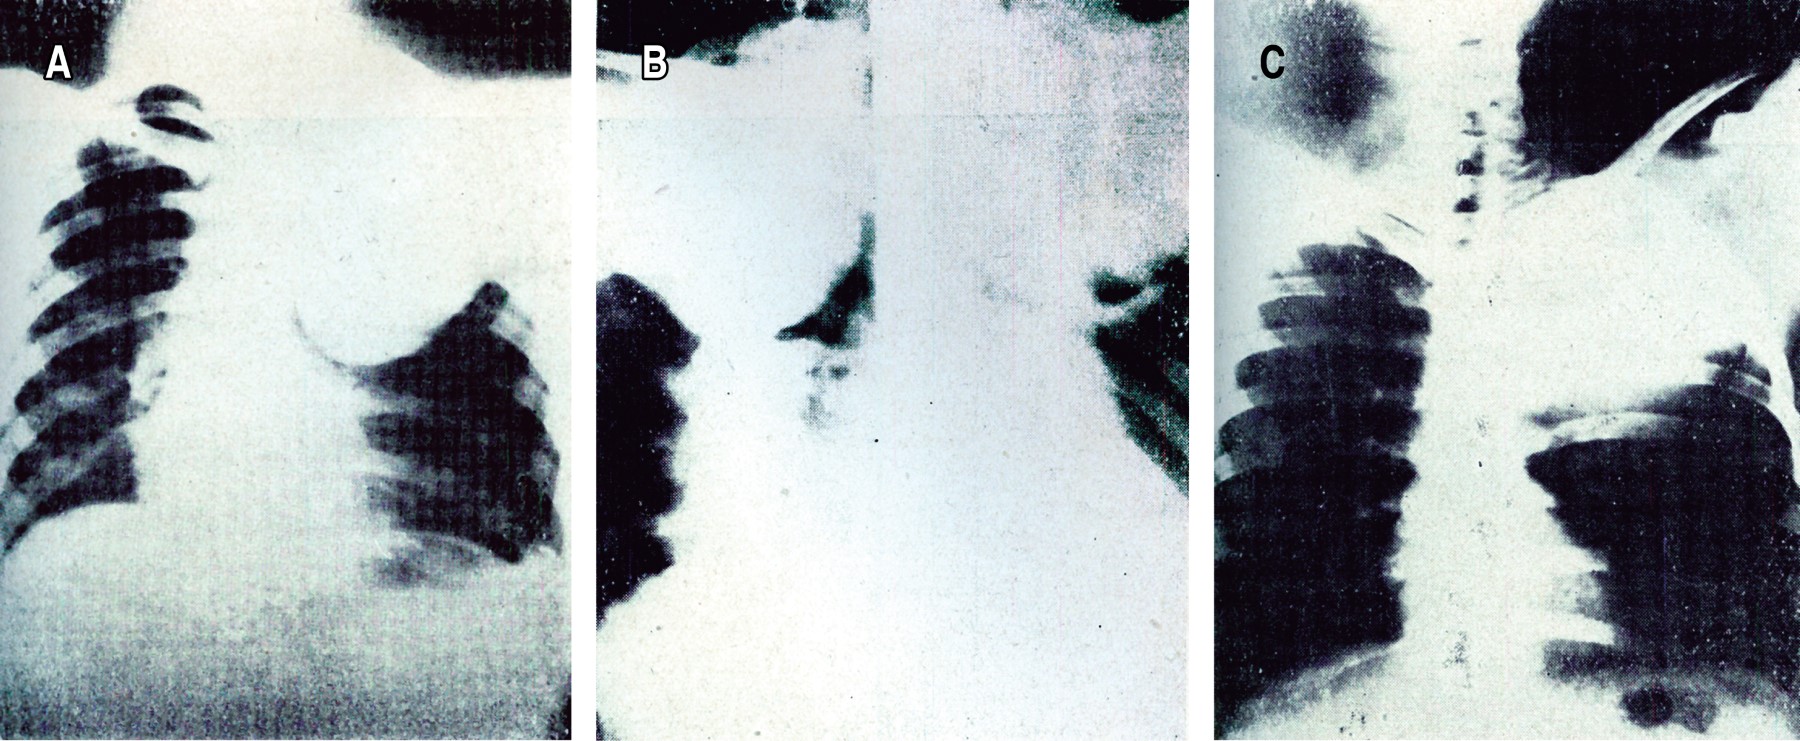

El primer artículo publicado en NCT que hace referencia específica y directa a la imagenología de tórax se titula "Estudio radiológico del cáncer pulmonar", de los doctores Alejandro Bandala y Alejandro Celis, publicado en el tercer número de la revista en 1939.2 Este artículo describe el uso de las proyecciones oblicuas y laterales en el diagnóstico de cáncer pulmonar, sus estrategias para el diagnóstico del derrame pleural concomitante, seguido de la neumoserosa con contraste, una técnica en la cual se instilaba material de contraste en la pleura con el objetivo de descubrir el proceso neoplásico subyacente (Figura 1). En 1940, el doctor Pedro L Fariñas de la Habana, Cuba, publica en NCT una conferencia dictada durante el Curso de Tuberculosis para Posgraduados del Sanatorio de Huipulco (INER) titulada: "Recientes progresos en el examen broncográfico del carcinoma primitivo del pulmón"; hace una descripción detallada de la broncografía, como único método para obtener información sobre la localización y extensión de las neoplasias pulmonares (Figura 2),3 con una amplia recomendación del estudio y hace uso de un léxico coloquial que permite entender el contexto humanista para su realización. El Dr. Fariñas describe en detalle: es esencial en la evaluación radiomorfológica y radiofisiológica; la broncografía con contraste brinda información explícita; hace referencia semiológica de la diseminación hemática, por contigüidad y linfática de las neoplasias pulmonares; narra la técnica de anestesia de la vía aérea, la introducción del catéter que permitía llegar al hemitórax a evaluar, con el paciente en decúbito lateral a explorar y la instilación del material de contraste (llamados aceites yodados o soluciones orgánicas de yodo), así como la toma de placas de "acecho" en el momento conveniente; discute sus desventajas; y, describe la correlación broncográfica con el análisis histopatológico.